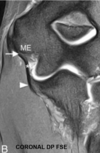

Q. De acuerdo con la imagen, qué signo radiológico identificas y en qué consiste.

Signo del ligamento colateral coronal. Consiste en la pérdida de la disposición oblicua del ligamento, observándolo completo en el un plano coronal, se observa en casos de inestabilidad estática de la rodilla comúnmente secundario a rotura del LCA.